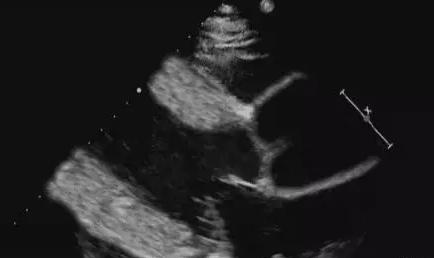

超音波診断のポイント

1.高血圧の既往歴が長い;

2.心室間隔および左室壁の均一な肥厚;

3.左心拡大;

4.左室壁運動の振幅の減少;

5.相対的僧帽弁閉鎖不全症。

識別:

高血圧性疾患による心室間隔の非対称性肥大は、主に病歴によって肥大型心筋症と区別されるが、この場合、心室間隔の心筋エコーは不均一で肉眼的にガラス状であるが、ほとんどが非典型的である。

高血圧による左心肥大と左心低形成は、超音波検査では冠動脈疾患によるものと区別が難しく、冠動脈造影、病歴、その他の臨床情報と組み合わせる必要があり、臨床治療の原則は基本的に同じであるため、左心肥大と左心低形成の超音波診断で十分である。